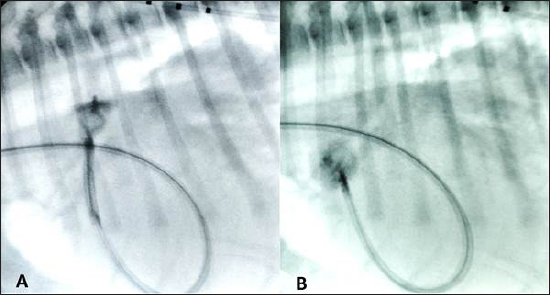

Fig. 1. Thoracic radiographs, right lateral and dorso-ventral views, (A and B) before the surgery and (C and D) 24 hours later. Post-operative films show a reduction of the cardiac silhouette and of the pulmonary over-circulation, and correct device position.

Anesthesia was induced and maintained as previously described (Bagardi et al., 2022) and perioperative intravenous amoxicillin (22 mg/kg) was administered. The dog was placed in left lateral recumbency on the fluoroscopy table, the right jugular vein was surgically isolated by a cut-down technique, and an 11 Fr, 10 cm long introducer vascular sheath (Pinnacle Peripheral Introducer Sheath, Terumo Medical Corporation, Somerset, NJ) was inserted into the jugular vein. A 4 Fr, 65 cm long diagnostic catheter (Berenstein Hockey stick tip catheter, Infiniti Medical, Huddersfield, UK) was then inserted into the jugular vein along with a preplaced straight tip hydrophilic 0.035″, 150 cm long guidewire (Terumo Radiofocus® Glidewire, Terumo Medical Corporation, Somerset, NJ). The guidewire and catheter were passed, under fluoroscopic guidance, through the right ventricle into the pulmonary artery and through the PDA in a retrograde manner until the tip of the catheter reached the descending aorta. After removing the guidewire, an angiographic study using 3 ml of iohexol (240 mg/ml), manually injected, was performed, showing the morphology of the PDA (length: 9 mm, maximal ampulla width:10.4 mm, minimal PDA diameter at the ostium: 5.4 mm). Following angiography, a standard stiffness 0.035″, 175 cm long J-tip guide wire (Medtronic Angiographic PTFE Rosen Wire, Medtronic Vascular, Danvers, MA) was advanced into the descending aorta and the diagnostic catheter was removed. A 7 Fr × 40 cm guiding sheath with a 2.54 mm inner diameter (Flexor Balkin KCFW-7.0-38-40-RB-BLKN-HC with Check-Flo Valve, Cook Medical Inc., Bloomington, IN) was advanced over the guidewire into the descending aorta to serve as a delivery sheath, and the guidewire was removed together with the dilator. A 16 mm AVPII was positioned via the delivery sheath into the PDA ampulla as previously described (Bagardi et al., 2022); however, an immediate “pull-through” into the pulmonary artery occurred before deployment (Fig. 3). The device was retracted and removed. Given the PDA morphology and the failure to secure the AVPII, we chose a 12 mm Amplatzer™ mVSD occluder device with a disc diameter of both discs of 20 mm, device waist size of 12 mm, and a length of connecting waist of 7 mm. This choice was based on the fact that the larger AVPII device is 18 mm wide and, given the ease and immediacy of pulling through, we thought that a device less than 2 mm wider would not have guaranteed against a post-operative embolization, even if successfully implanted. Furthermore, the next-sized AVPII (18 mm) is twice as long as the mVSD (14 vs. 7 mm). We considered that larger AVPII devices could have obstructed the aorta or pulmonary artery, as has been described in children (Salam et al., 2022).